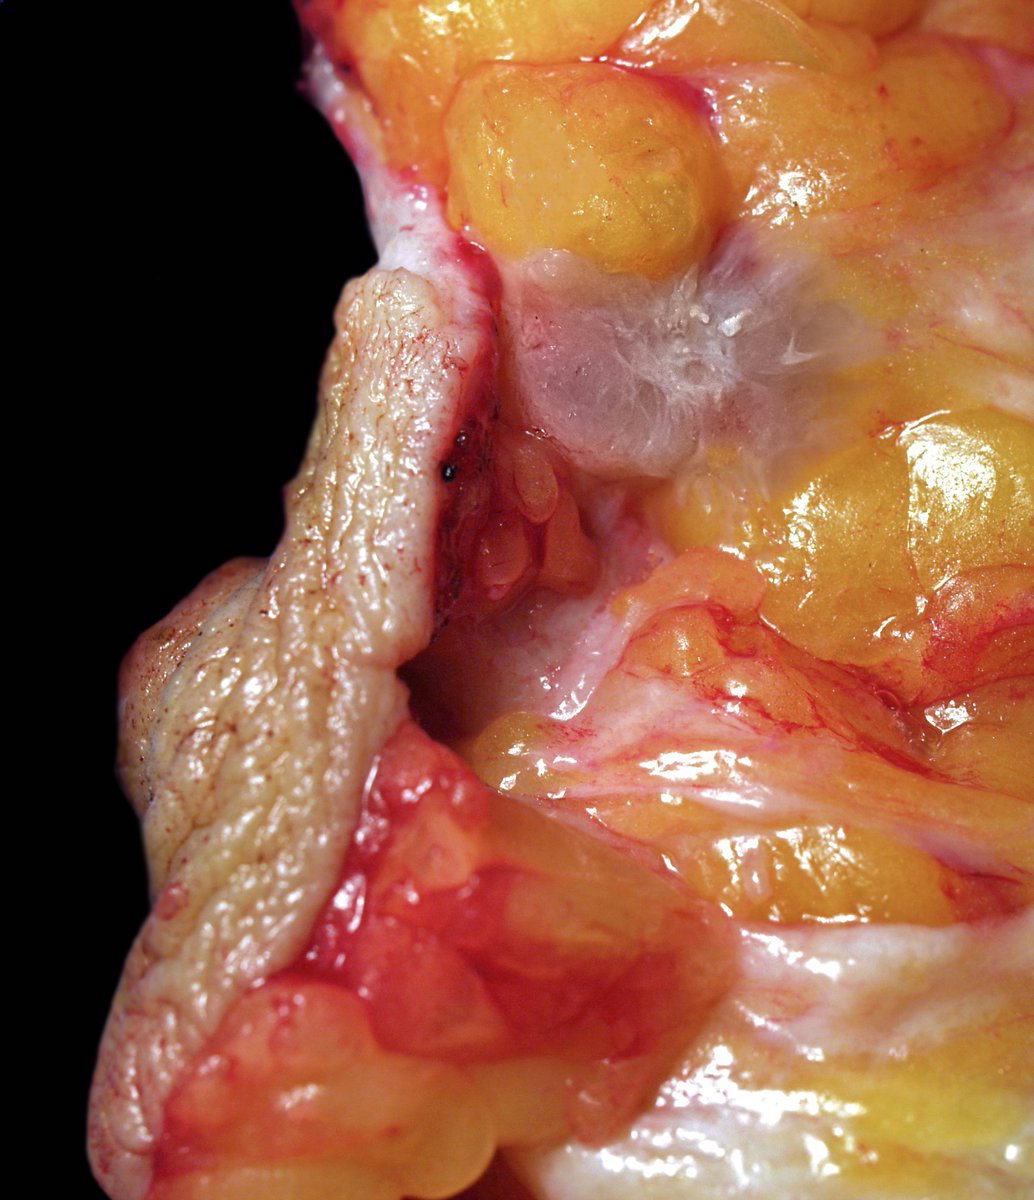

Gross description

- Grossly evident mass, with an irregular, stellate outline or nodular configuration

- Mass is usually poorly circumscribed and contracts from surrounding tissue

- Firm or even hard on palpation and may have a gritty feel when cut with a knife, grating sound when scraped

- May show streaks of chalky white elastotic stroma penetrating surrounding stroma (crab-like), calcification

- Large tumors have hemorrhage, necrosis and cystic degeneration

- May be fixed to chest wall and cause skin dimpling or nipple retraction

- Some tumors, including neoadjuvant treated cancers, may be grossly inapparent and require careful correlation with the imaging at the time of gross examination and tissue sampling